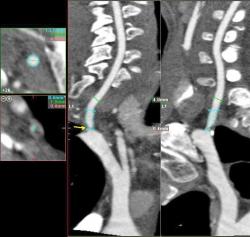

Мужчина, 62 года. Перенес ишемический инсульт в бассейне правой средней мозговой артерии.

На КТ-ангиографии выявлена окклюзия правой внутренней сонной артерии в области развилки в виде паламени свечи (красная стрелка), стеноз высокой степени в устье правой вертебральной артерии (желтая стрелка), небольшой перегиб в устье левой вертебральной артерии (голубая стрелка).

Вы отчасти правы. Инсульт пациент перенес давно, тогда не было возможности ни диагностировать, не лечить. Сейчас ему планируют установить стент в правую позвоночную артерию.

Больному успешно установлен стент в устье правой вертебральной артерии.